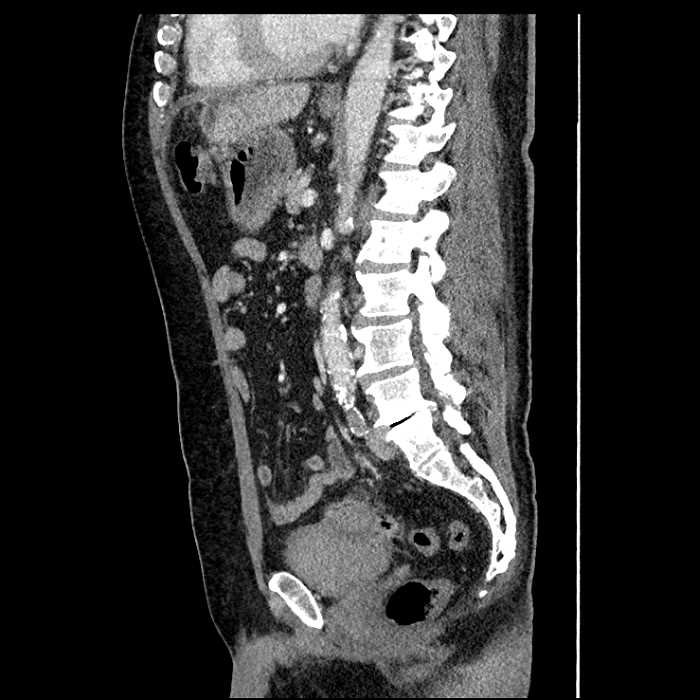

• Mild mural thickening of a segment of the sigmoid colon with adjacent fat stranding and a 1.5 cm fluid and gas collection along the tip of an inflamed diverticulum

• Loss of the normal fat plane between this collection and adjacent loops of small bowel, which demonstrate mural thickening

• High grade stenosis of the left common iliac artery, with the left internal and external iliac arteries remaining patent

Acute sigmoid diverticulitis complicated by a small contained perforation and a large abscess in the right hepatic lobe. Additional small subcapsular abscesses along the anterior margin of the left hepatic lobe.

Additionally, loss of the normal fat plane between the peridiverticular collection and adjacent thickened loops of small bowel raises the potential for an enterocolonic fistula.

High grade stenosis of the left common iliac artery. The left external and internal iliac arteries are patent.

Hepatic abscess showing the double target sign with low density internally surrounded by a thin inner enhancing rim (red arrow) and ill-defined outer low density rim (yellow arrow). Blue arrow indicates an internal septation. Red arrows: additional smaller subcapsular abscesses. Red arrow: focal contained perforation associated with diverticulitis.